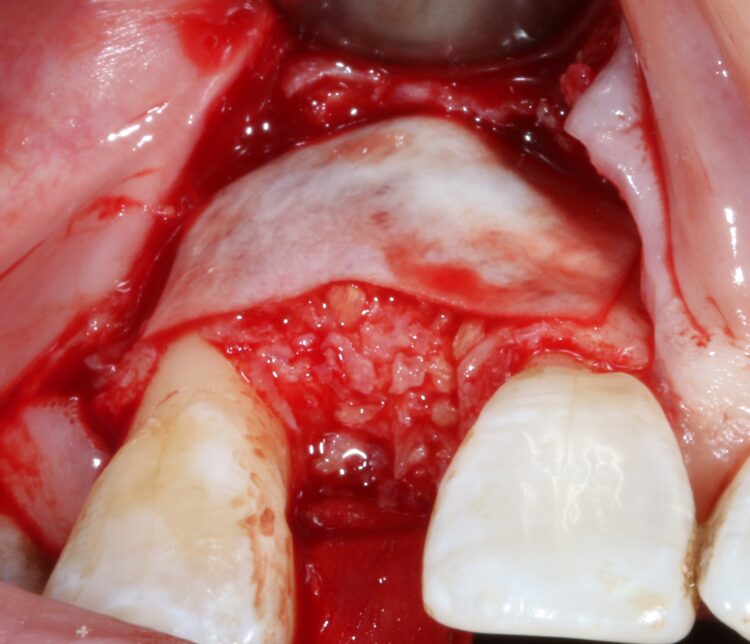

The first treatment phase included the elevation of a large full thickness flap to fully expose the area and enable the harvesting of autogenous bone utilising a safescraper.

The UR2 was then removed including excavation of all granulation tissue, taking care to avoid any direct curettage of the exposed UR3 root. The large bone defect was then filled with a 50/50 mix of autogenous bone chips and an allograft (MinerOss®, a cortico-cancellous mix – BioHorizons Camlog) and the buccal defect was covered with a native porcine collagen membrane with a high percentage of collagen type III for a prolonged barrier function of six months. No fixation pins were used.

The concept was that this exposed membrane would provide a barrier and prevent loss of the bone graft, but would also break down rapidly, favouring early epithelialisation of the open wound by secondary intention healing.

The occlusal aspect of the bone graft – which would remain exposed during the healing period – was covered with a shorter acting native collagen membrane. The concept was that this exposed membrane would provide a barrier and prevent loss of the bone graft, but would also break down rapidly, favouring early epithelialisation of the open wound by secondary intention healing.

The muco-periosteal flap was sutured back with 6.0 Prolene and no attempt was made to coronally advance the flap for complete closure. The rationale was to maintain the open socket wound and thereby preserve the original mucogingival relationship with no alteration. The socket entrance was sealed with the short acting membrane, while the original tooth (after root removal) was utilised as a temporary pontic and bonded to the adjacent teeth with flowable composite.